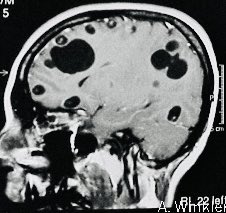

Man with history of eating undercooked pork presents with seizures Diagnosis ❔